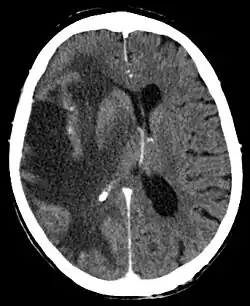

Bei quantitativen Bewusstseinsstörungen und allgemeinen Zeichen des gesteigerten Hirndrucks bietet sich nach der Anamneseerhebung und neurologischen Untersuchung eine Ophthalmoskopie an, die bei positivem Ausfall eine Stauungspapille zeigen würde. Sicherheit gibt die bildgebende Untersuchung des Schädelinneren durch eine Computertomographie oder Kernspintomographie.